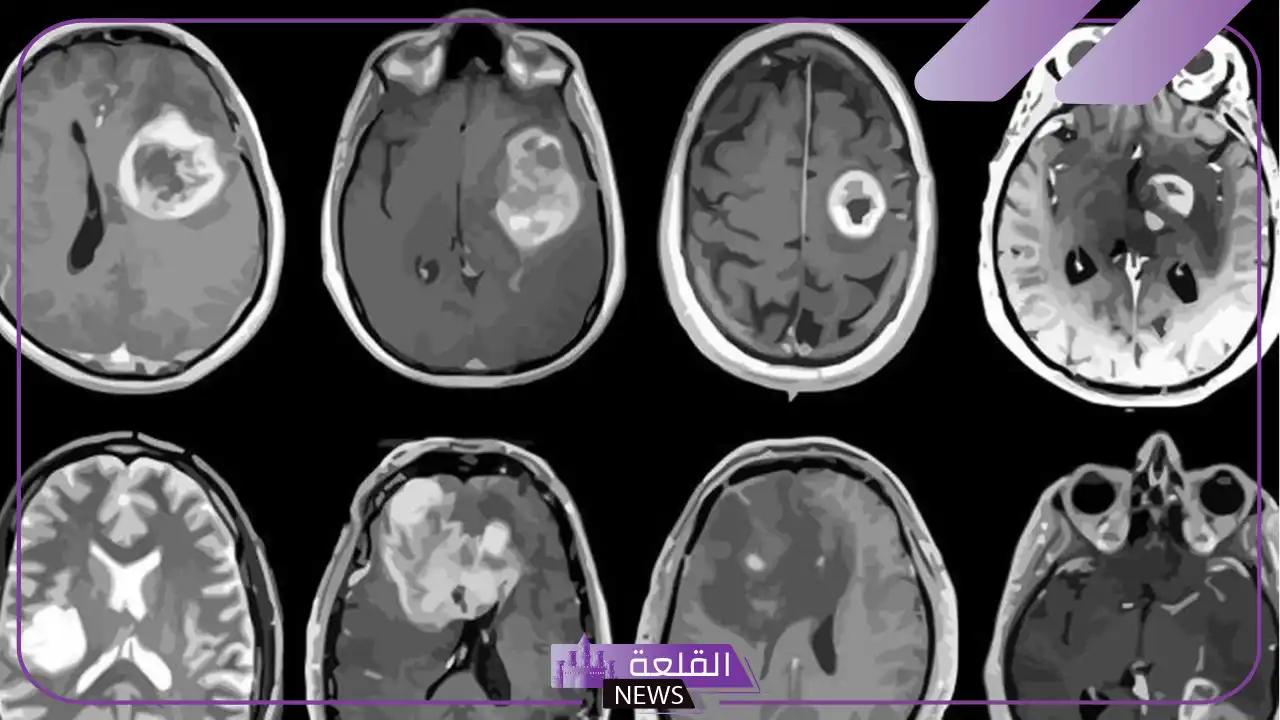

ورم الدماغ هو نمو غير طبيعي للخلايا في الدماغ، وقد يكون حميدًا أو خبيثًا، مما يؤثر على وظائف الدماغ الحيوية ويُعتبر من الأمراض الخطيرة والقوية والتي تحتاج إلى تعامل خاص وهو ما دفعني اليوم لكي أطرح تجربتي بصورة مُفصلة.

تجربتي مع ورم الدماغ

كنت أعيش حياة طبيعية مليئة بالأحلام والخطط، فجأة انقلب العالم رأسًا على عقب حينما اكتشفتُ أنني أعاني من ورم في الدماغ، في أول الأمر شعرت بالصدمة والخوف وتخيلت أسوأ السيناريوهات، ولكنني قررت ألا أستسلم ومع مساعدة عائلتي وأصدقائي وبدعم الفريق الطبي المتميز خضعت للعلاج، لم انكر كانت رحلة صعبة ومليئة بالتحديات لكنها علمتني الكثير عن قوة الإرادة والتفاؤل، واليوم أنا هنا أحكي قصتي وتجربتي وأشكر الله على كل لحظة.